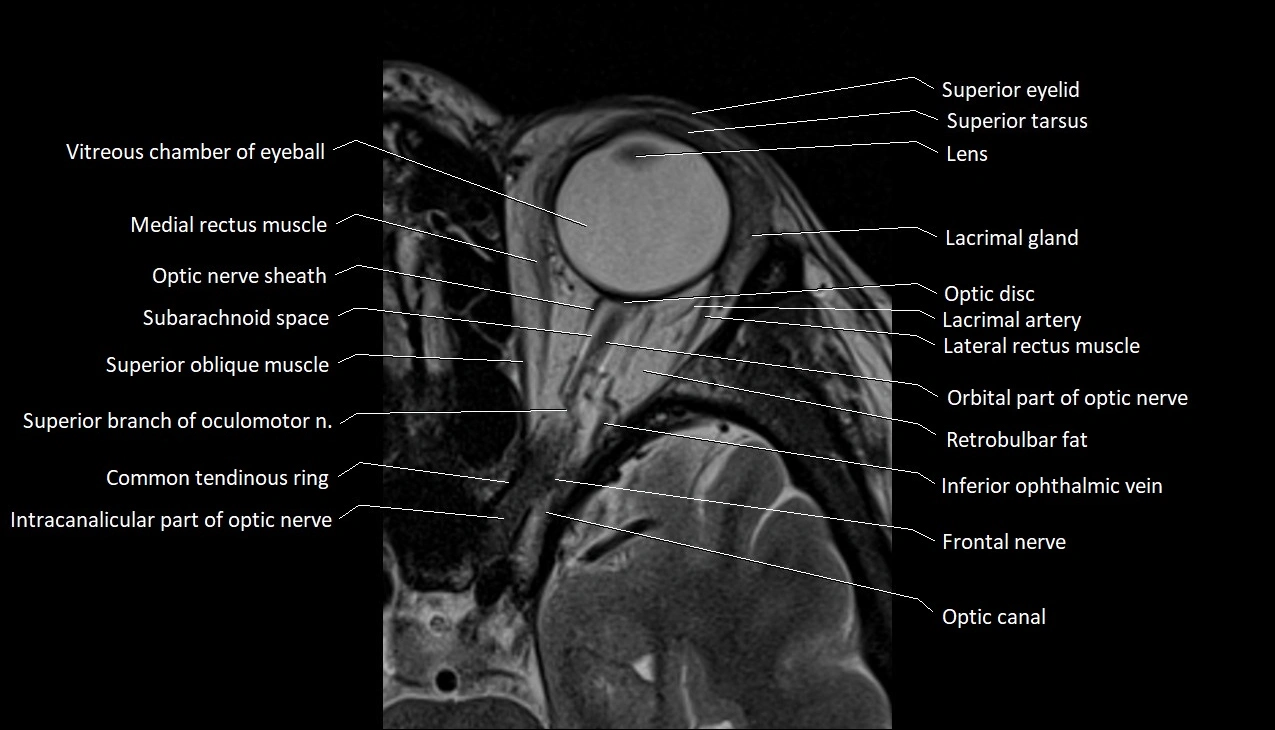

MRI images